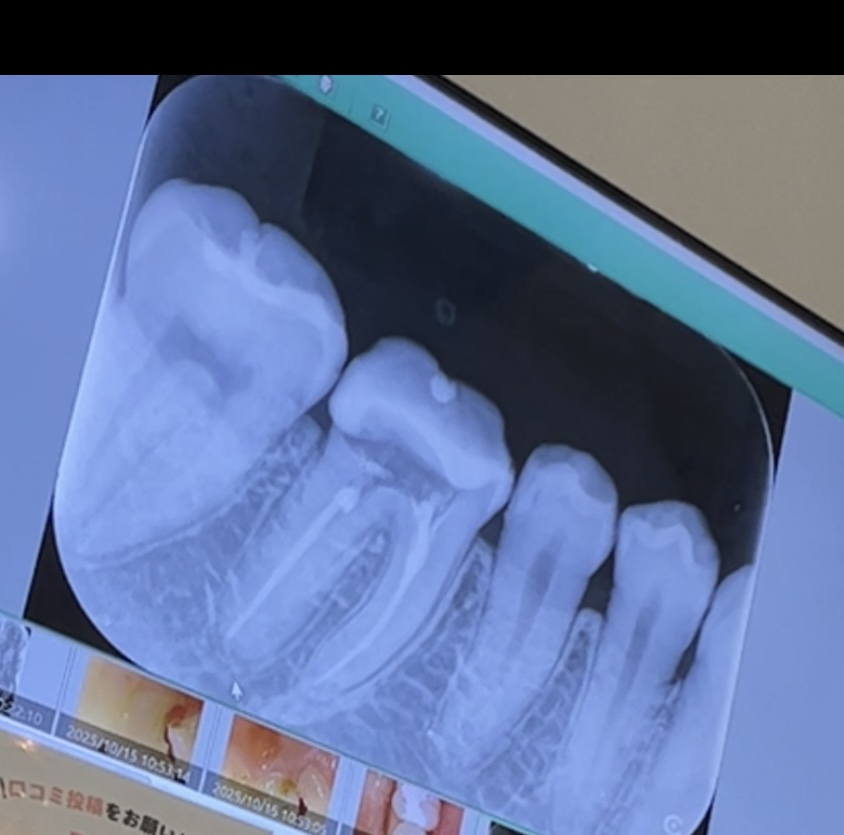

神経を抜いた歯が痛むようになりました。治療は何が最善ですか?